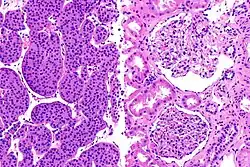

Jest to dobrze zróżnicowany nowotwór łagodny. Wywodzi się z kanalików nerkowych bliższych z komórek wstawkowych przewodów zbiorczych[1]. Guz jest zbudowany z dużych komórek o obfitej i ziarnistej eozynochłonnej (kwasochłonnej) cytoplazmie, małych jądrach i licznych mitochondriach (tzw. onkocytów[2]). Komórki układają się w formie tworów cewkowych lub pęcherzykowych[1].